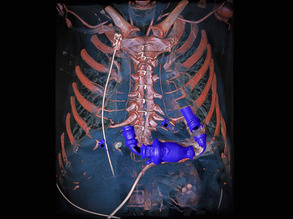

Your Bleeping Heart